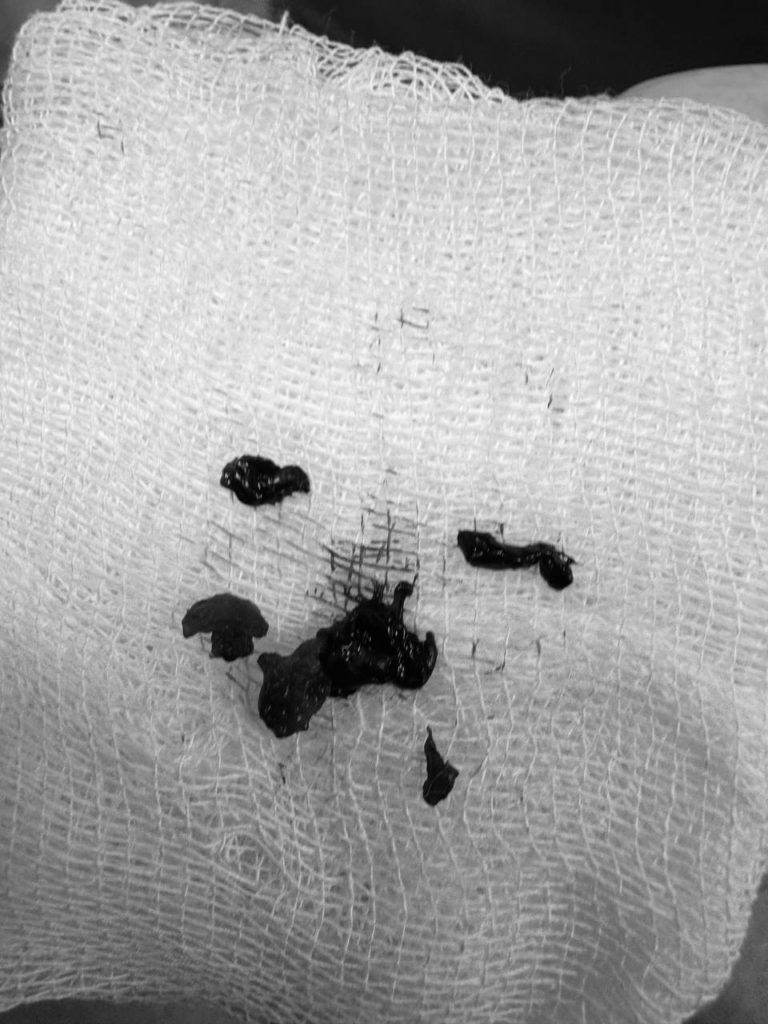

Єдиним шансом на порятунок стало ендоваскулярне втручання — через судину під контролем рентгену. Команда інтервенційних кардіологів, анестезіологів і реаніматологів виконала тромбаспірацію. Це сучасне малоінвазивне втручання, яке дозволяє механічно видалити тромб без відкритої операції. Цей метод лікарі Першого медичного об’єднання Львова опанували під час міжнародного конгресу інтервенційних радіологів у Барселоні і застосовували вперше.

“Це перші успішні тромбаспірації при ТЕЛА, виконані у нашому медоб’єднанні. Ми довели, що Львів має не лише серце, яке допомагає, але й серця, які рятують”, — наголошує завідувач відділення кардіології та реперфузійної терапії Центру серця та судин Лікарні Святого Пантелеймона Василь Процько.